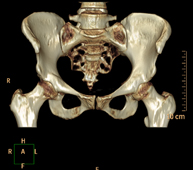

Exploració radiològica que mitjançant un sistema de raigs X i detectors que giren al voltant del pacient i que reconstrueixen les imatges per ordinador (TC Multidetector), permet l'estudi detallat dels ossos, els músculs i les articulacions de la mà i el canell. - TC de la pelvis òssia

Exploració radiològica que mitjançant un sistema de raigs X i detectors que giren al voltant del pacient i que reconstrueixen les imatges per ordinador (TC Multidetector), permet l'estudi detallat dels ossos, els músculs i les articulacions de la pelvis. - TC de malucs

Exploració radiològica que mitjançant un sistema de raigs X i detectors que giren al voltant del pacient i que reconstrueixen les imatges per ordinador (TC Multidetector), permet l'estudi detallat dels ossos, els músculs i les articulacions del maluc. - TC de sacroilíaques

Exploració radiològica que mitjançant un sistema de raigs X i detectors que giren al voltant del pacient i que reconstrueixen les imatges per ordinador (TC Multidetector), permet l'estudi detallat de les articulacions sacroilíaques i descartar malalties inflamatòries, traumàtiques o degeneratives. - TC de genoll